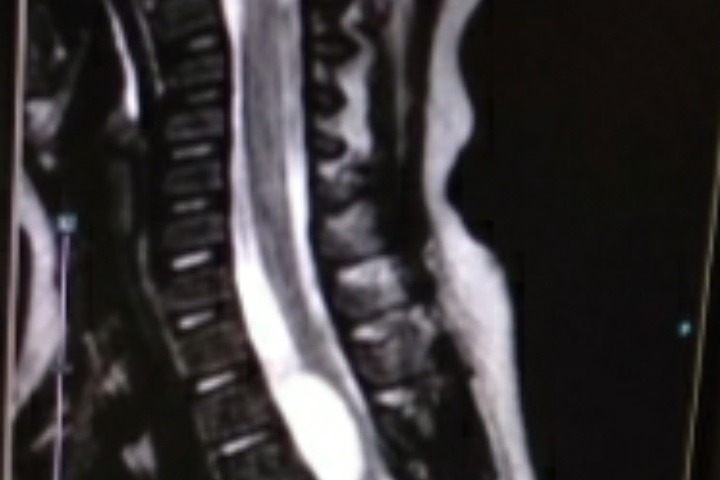

However, a parent's worst nightmare was met when on October 8th, Fletcher woke up and was paralysed from the chest down. He was immediately taken in for an MRI and his family were told there was a "tumour" between his T1 and T5 vertebrae, compressing his spinal cord, which caused the paralysis to set in.

In March of this year, after a follow up MRI, it was determined that Fletchers tumour/cyst (the mass is still unidentified) has refilled, he has another cord compression and is about to go through a more extensive surgery to try and resect and prevent this from happening again. The surgery will be performed at a higher vertebrae, which means there is higher risks, namely quadriplegia.